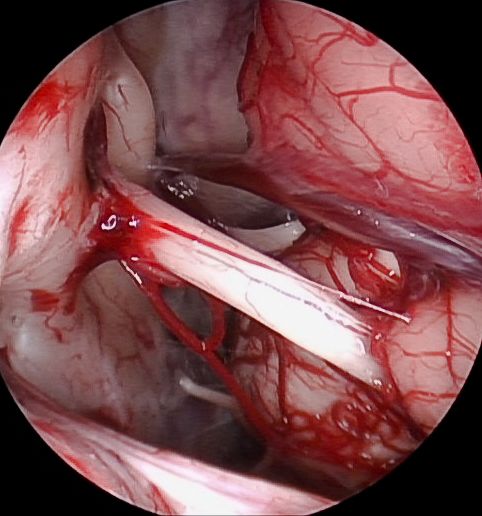

Die Schlüssellochchirurgie findet auch in der Neurochirurgie zunehmend Anwendung. Obwohl der Einsatz des Endoskops aufgrund anatomischer Gegebenheiten nicht für alle Erkrankungen geeignet ist, gibt es zahlreiche Indikationen, bei denen diese Technologie von großer Bedeutung ist. Besonders hervorzuheben sind intraventrikuläre Pathologien, wie etwa Erkrankungen des Hirnkammersystems (z.B. Hydrocephalus), die Chirurgie an peripheren Nerven, transsphenoidale Operationen sowie die unterstützende Visualisierung in der Schädelbasischirurgie. Je nach Indikation kommen moderne Neuroendoskopiegeräte der Firmen Braun und Storz mit ergänzender HD-Technologie zum Einsatz. Sowohl pädiatrische als auch erwachsene Patienten profitieren von den minimal-invasiven Eingriffen, die mit kleinen Hautschnitten und einer schnelleren Genesung verbunden sind.